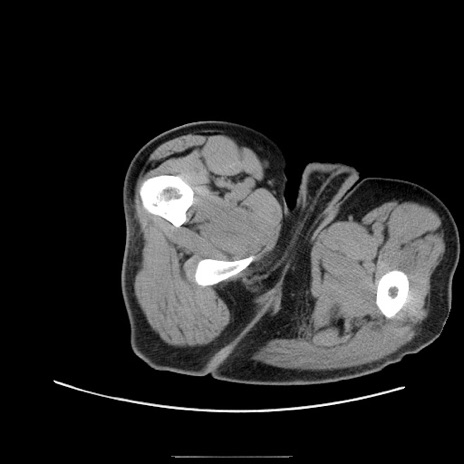

冠状断像

【症例】50歳代男性

【主訴】腹痛

【現病歴】AVMからの被殻出血のため回復期リハ病棟入院中。 本日午後3時頃急に下腹部痛が出現した。

【既往歴】AVM、被殻出血、虫垂炎、高血圧

【身体所見】意識晴明、左半身不全麻痺、会話の理解は良好、36.5°C、腹部:膨隆、全体に板状硬、下腹部正中に圧痛点あり、反跳痛-、筋性防御不明、右下腹部にope scar

【データ】WBC 9400、CRP 0.06